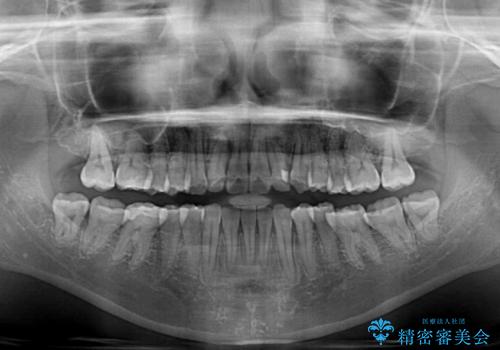

診査を行ったところ、下顎前歯が1本欠損しており、下顎歯列が上顎よりも小さくなっていることで、上顎にデコボコが生じていました。

口元を見ると抜歯をして突出感を改善するような状態ではなかったため、上顎歯列のデコボコを整えて、歯列全体を後方に移動させることでバランスを取ることとしました。

思っていた以上に上顎歯列を後方に移動させることができ、すっきりとした口元に仕上げることができました。